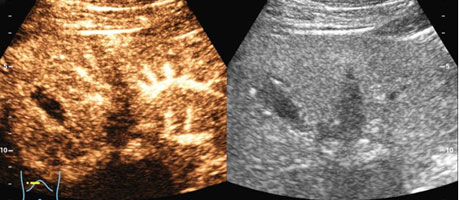

在超声造影检查前,二维超声检查可见患者肝左内叶胆囊旁低回声结节,大小为2.0cm×1.1cm,形态稍欠规则,边界清,结节内部未见明显血流。经患者左侧肘部静脉注入超声造影剂后,发现肝内结节与周围肝实质三期同步增强,考虑结节为良性病变,肝内结节是由于肝内脂肪沉积不均所致。检查过程持续10 分钟,造影结束后留观 15 分钟,患者无不良反应后拔出静脉穿刺针,检查结束。得知自己肝内结节考虑是良性病变,只需定期复查时,压在王先生心里的一块大石头终于落地了。

通过造影剂,可实时动态观察结节内部的微循环血流灌注情况,做出诊断